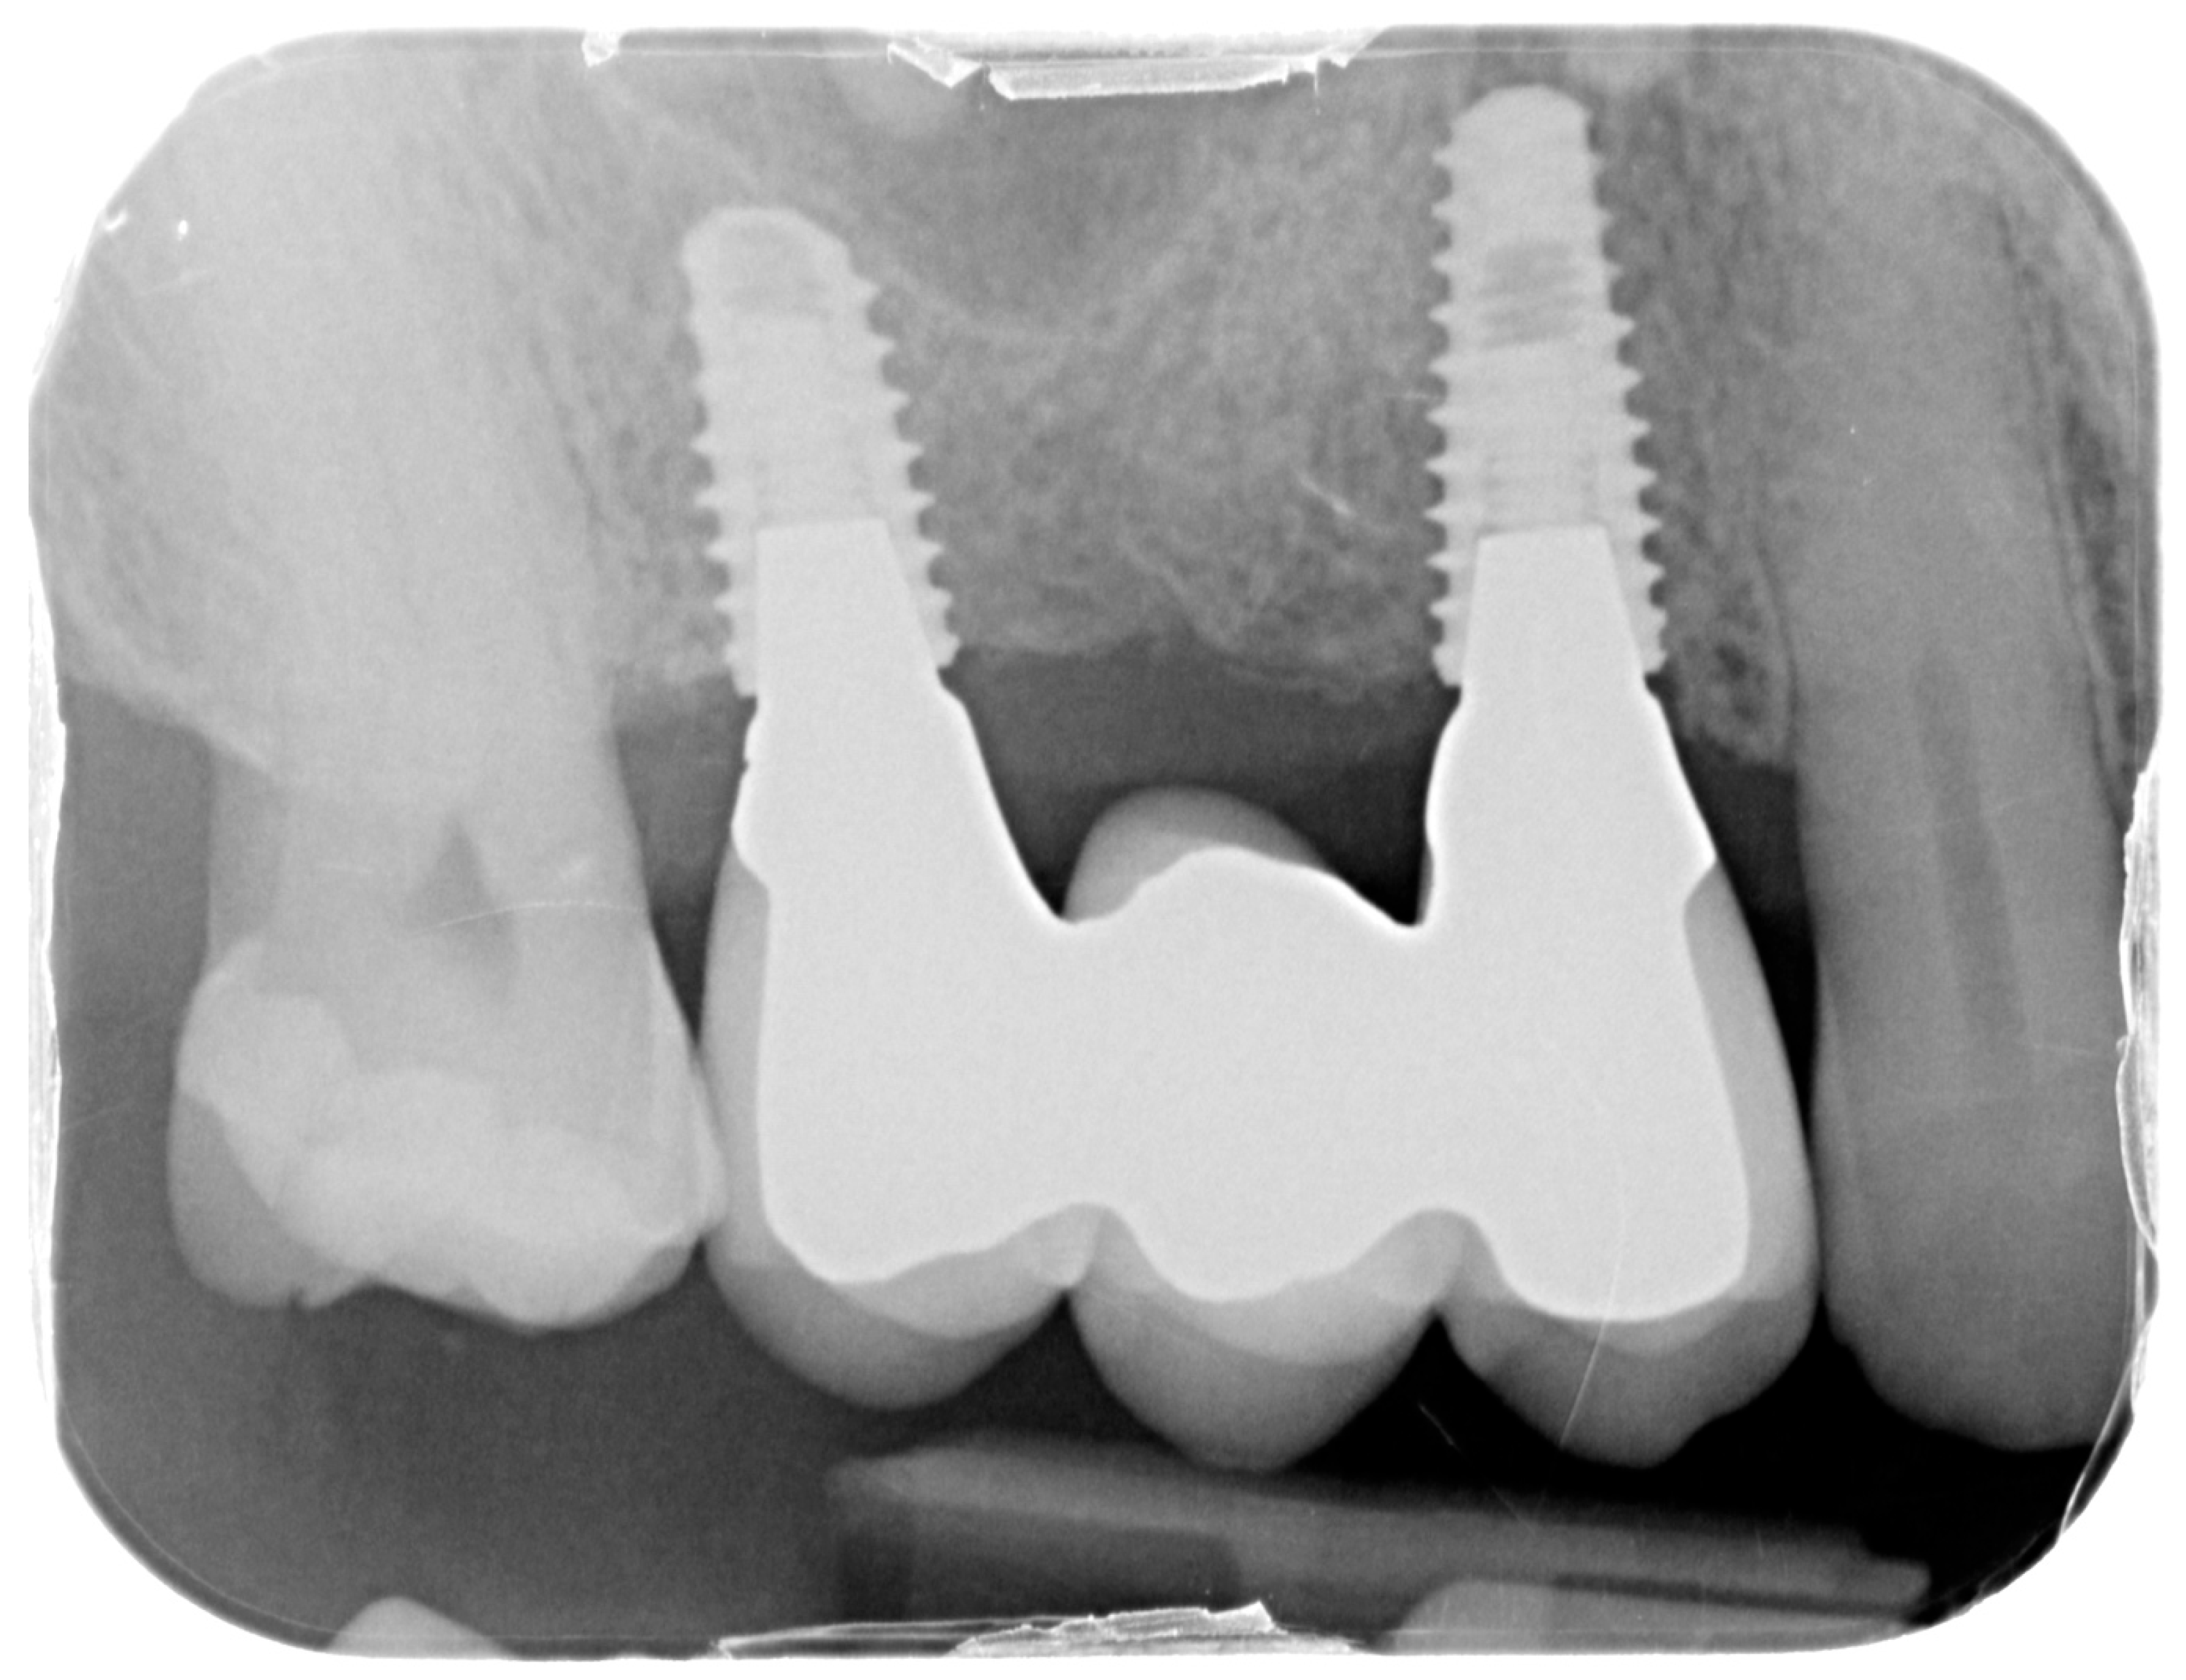

Figure 13.

Intraoral X-ray at one year follow-up.

For the evaluation of the mesial and distal MBL, intraoral digital radiographs were taken using the long-cone paralleling technique with the central beam directed to the alveolar crest. Periapical radiographs were taken at the delivery of the prosthesis and after 1 year of prosthetic loading (T2). The mesial and distal MBL, i.e., the distance between the top of the implant shoulder and the first visible bone-to-implant contact, were measured at the mesial and distal aspect with a 10–15× magnification using an image analysis programme (ImageJ v 1.49, NIH, Bethesda, MA, USA). The length of the implant was used as known measure for the calibration and determination of the exact magnification and distortion of the images. All measurements were performed by two examiners to the nearest 0.1 mm. In case of disagreement, the evaluation was re-done and results discussed until an agreement was found.

The status of peri-implant hard and soft tissues was assessed at T2, one year from the prosthetic loading. Data of 17 participants and 25 surgical sites were available, as one drop-out was recorded. The patient moved to another city and was not available for the follow-up recall. The overall mean MBL considering both mesial and distal aspects was 0.54 ± 0.7 mm. The mean BoP rate was 38.1%, while the mean PPD was 2.79 ± 0.78 mm with a maximum value of 4.5 mm. There were no statistically significant differences in MBL, PPD, BoP, or KMW based on BBT (p > 0.05). The correlation between BBT and clinical outcomes was weak and not statistically significant. Specifically, thicker buccal bone was associated with a slight reduction in PPD (coefficient: −0.33), but this effect was not statistically significant (p > 0.05). In contrast, BoP was strongly associated with increased PPD (coefficient: 1.04, p < 0.001), indicating that patients with higher BoP scores tended to have deeper PPD. There was no significant effect of KMW on PPD (p > 0.05).